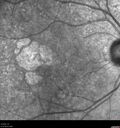

Geographic Atrophy with Vision Change

80 year old female Recent vision loss in the left eye for about 6 weeks.

VA 20/25 OD, 20/63 OS (was 20/40 5/3/21 at patients first visit)